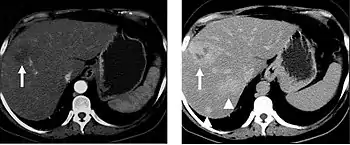

The late arterial phase is timed to correspond to the peak concentration of contrast material in highly vascular tumors and is performed approximately 20–35 seconds after the injection of intravenous contrast. Early arterial phase imaging is predominantly utilized for angiography and will be discussed separately. Late arterial phase imaging is almost always performed in conjunction with other phases (e.g. portal venous phase) to allow more complete characterization of any identified abnormalities (figure 4). The primary indication for a late arterial phase is for the evaluation of hypervascular tumors of the liver such as hepatocellular carcinoma or hypervascular metastases (figure 4). Typical hypervascular tumors for which this would be used include: hepatocellular carcinoma; renal cell carcinoma; melanoma; carcinoid/neuroendocrine tumors; some sarcomas; choriocarcinoma; and thyroid carcinoma. Although a “hypervascular”, biphasic evaluation would generally be used for these patients, note that a single phase is often adequate for follow up imaging.

Liver masses

When evaluating hepatic masses, it can be advantageous to have both late arterial and portal venous phase images (biphasic imaging, figure 4) since some tumors enhance briskly during the arterial phase (hepatocellular carcinoma, hepatic adenoma, follicular nodular hyperplasia (FNH), and hypervascular metastasis), but may be occult or difficult to characterize on portal venous phase imaging alone (figure 6). However, it should be stressed that the addition of late arterial phase images is only indicated if one of these tumors is suspected, or if there is a need for further characterization of a hepatic mass, since the large majority of patients will not benefit from the addition of this phase. In addition, if there is a need to definitively characterize a hepatic mass, MRI is generally more sensitive and specific, with no associated radiation dose.